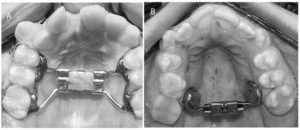

228 – Impacto de la CBCT en la toma de decisión del tratamiento relacionado a extracción de terceros molares impactados.

El objetivo del presente estudio fue evaluar los factores (referidos a la CBCT) que influyen en la toma de decisión en tratamientos para extracción de